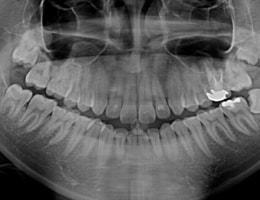

大きなパノラマレントゲンは歯並びなど、全体像をつかむことにも有効的ですが、

現状を詳細に把握するため、小さいレントゲンを10枚撮って診断・治療をしております。

これにより歯石、歯周ポケット等も詳細に把握でき、緻密な治療を提供することが出来ます。